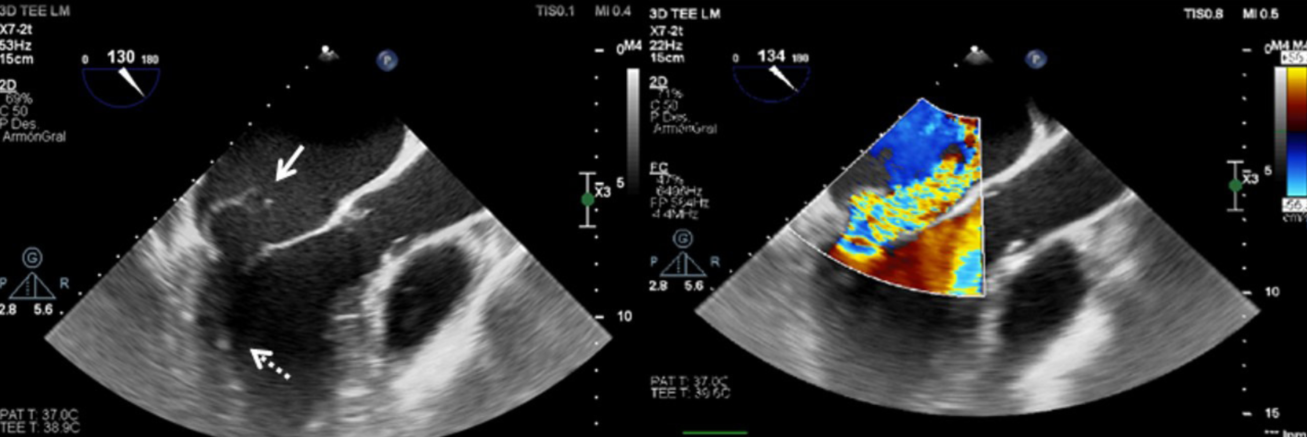

Se realiza un ecocardiograma transtorácico en el que se observan cavidades izquierdas dilatadas, función sistólica conservada con FEVI de 65% y una imagen sugestiva de vegetación a nivel de válvula mitral que presentaba insuficiencia severa. Posteriormente, se realiza un ecocardiograma transesofágico (figura 2) que evidenció una válvula mitral con anillo de 47 mm donde se observaba flail a nivel de festones P2 y P3 con rotura cordal e insuficiencia severa y una masa de 10 mm × 7 mm, algodonosa, móvil, adherida al aparato cordal del músculo posterolateral. Con estos hallazgos, se inicia tratamiento antibiótico por vía parenteral con base en cefazolina.

A. Ecocardiograma transesofágico a nivel de esófago medio. El eje largo del tracto de salida del ventrículo izquierdo está dilatado. La flecha continua indica flail de la valva menor de la válvula mitral. Se puede apreciar pequeña vegetación a nivel del aparato subvalvular (flecha punteada). B. Doppler color en el que se observa un jet de insuficiencia mitral severa excéntrica que ocupa gran parte de la aurícula izquierda que se encuentra dilatada.